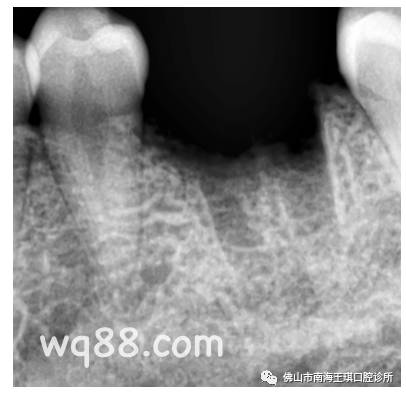

还不好拔。牙挺一碰,就碎了好多片,可以明确的看到底部烂得相当严重。

分根来拔,牙槽骨都有明显的吸收。

考虑到本身的炎症很重,这种情况我还是建议让他延期一两个月后再做种植。